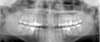

Une radio panoramique dentaire est un cliché radiographique de l'ensemble de la denture et des articulations temporo mandibulaires.

Toutes les dents sont donc visibles sur le même cliché ainsi que :

- Les arcades dentaires

- Les maxillaires supérieurs et inférieurs

- La partie basse des fosses nasales

- Le plancher des sinus maxillaires

En plus de l'étude des soins déjà effectués, ou à effectuer, sur les dents (traitement de caries, couronnes…), la panoramique dentaire permet de dépister les problèmes éventuels des dents, des maxillaires et des sinus, en particulier :

- Les caries

- La position des dents de sagesse dans les maxillaires

- L'existence de kystes dentaires à l'extrémité des racines

- Les dents surnuméraires

- Les agénésies dentaires (absence des germes des dents)

- L'évaluation générale de la perte de l'os de soutien des dents (parodontite)

- Les tumeurs

L’examen permet également de localiser l'emplacement des cavités naturelles (avant d'envisager la pose d'un implant dentaire par exemple) et le trajet du nerf mandibulaire.